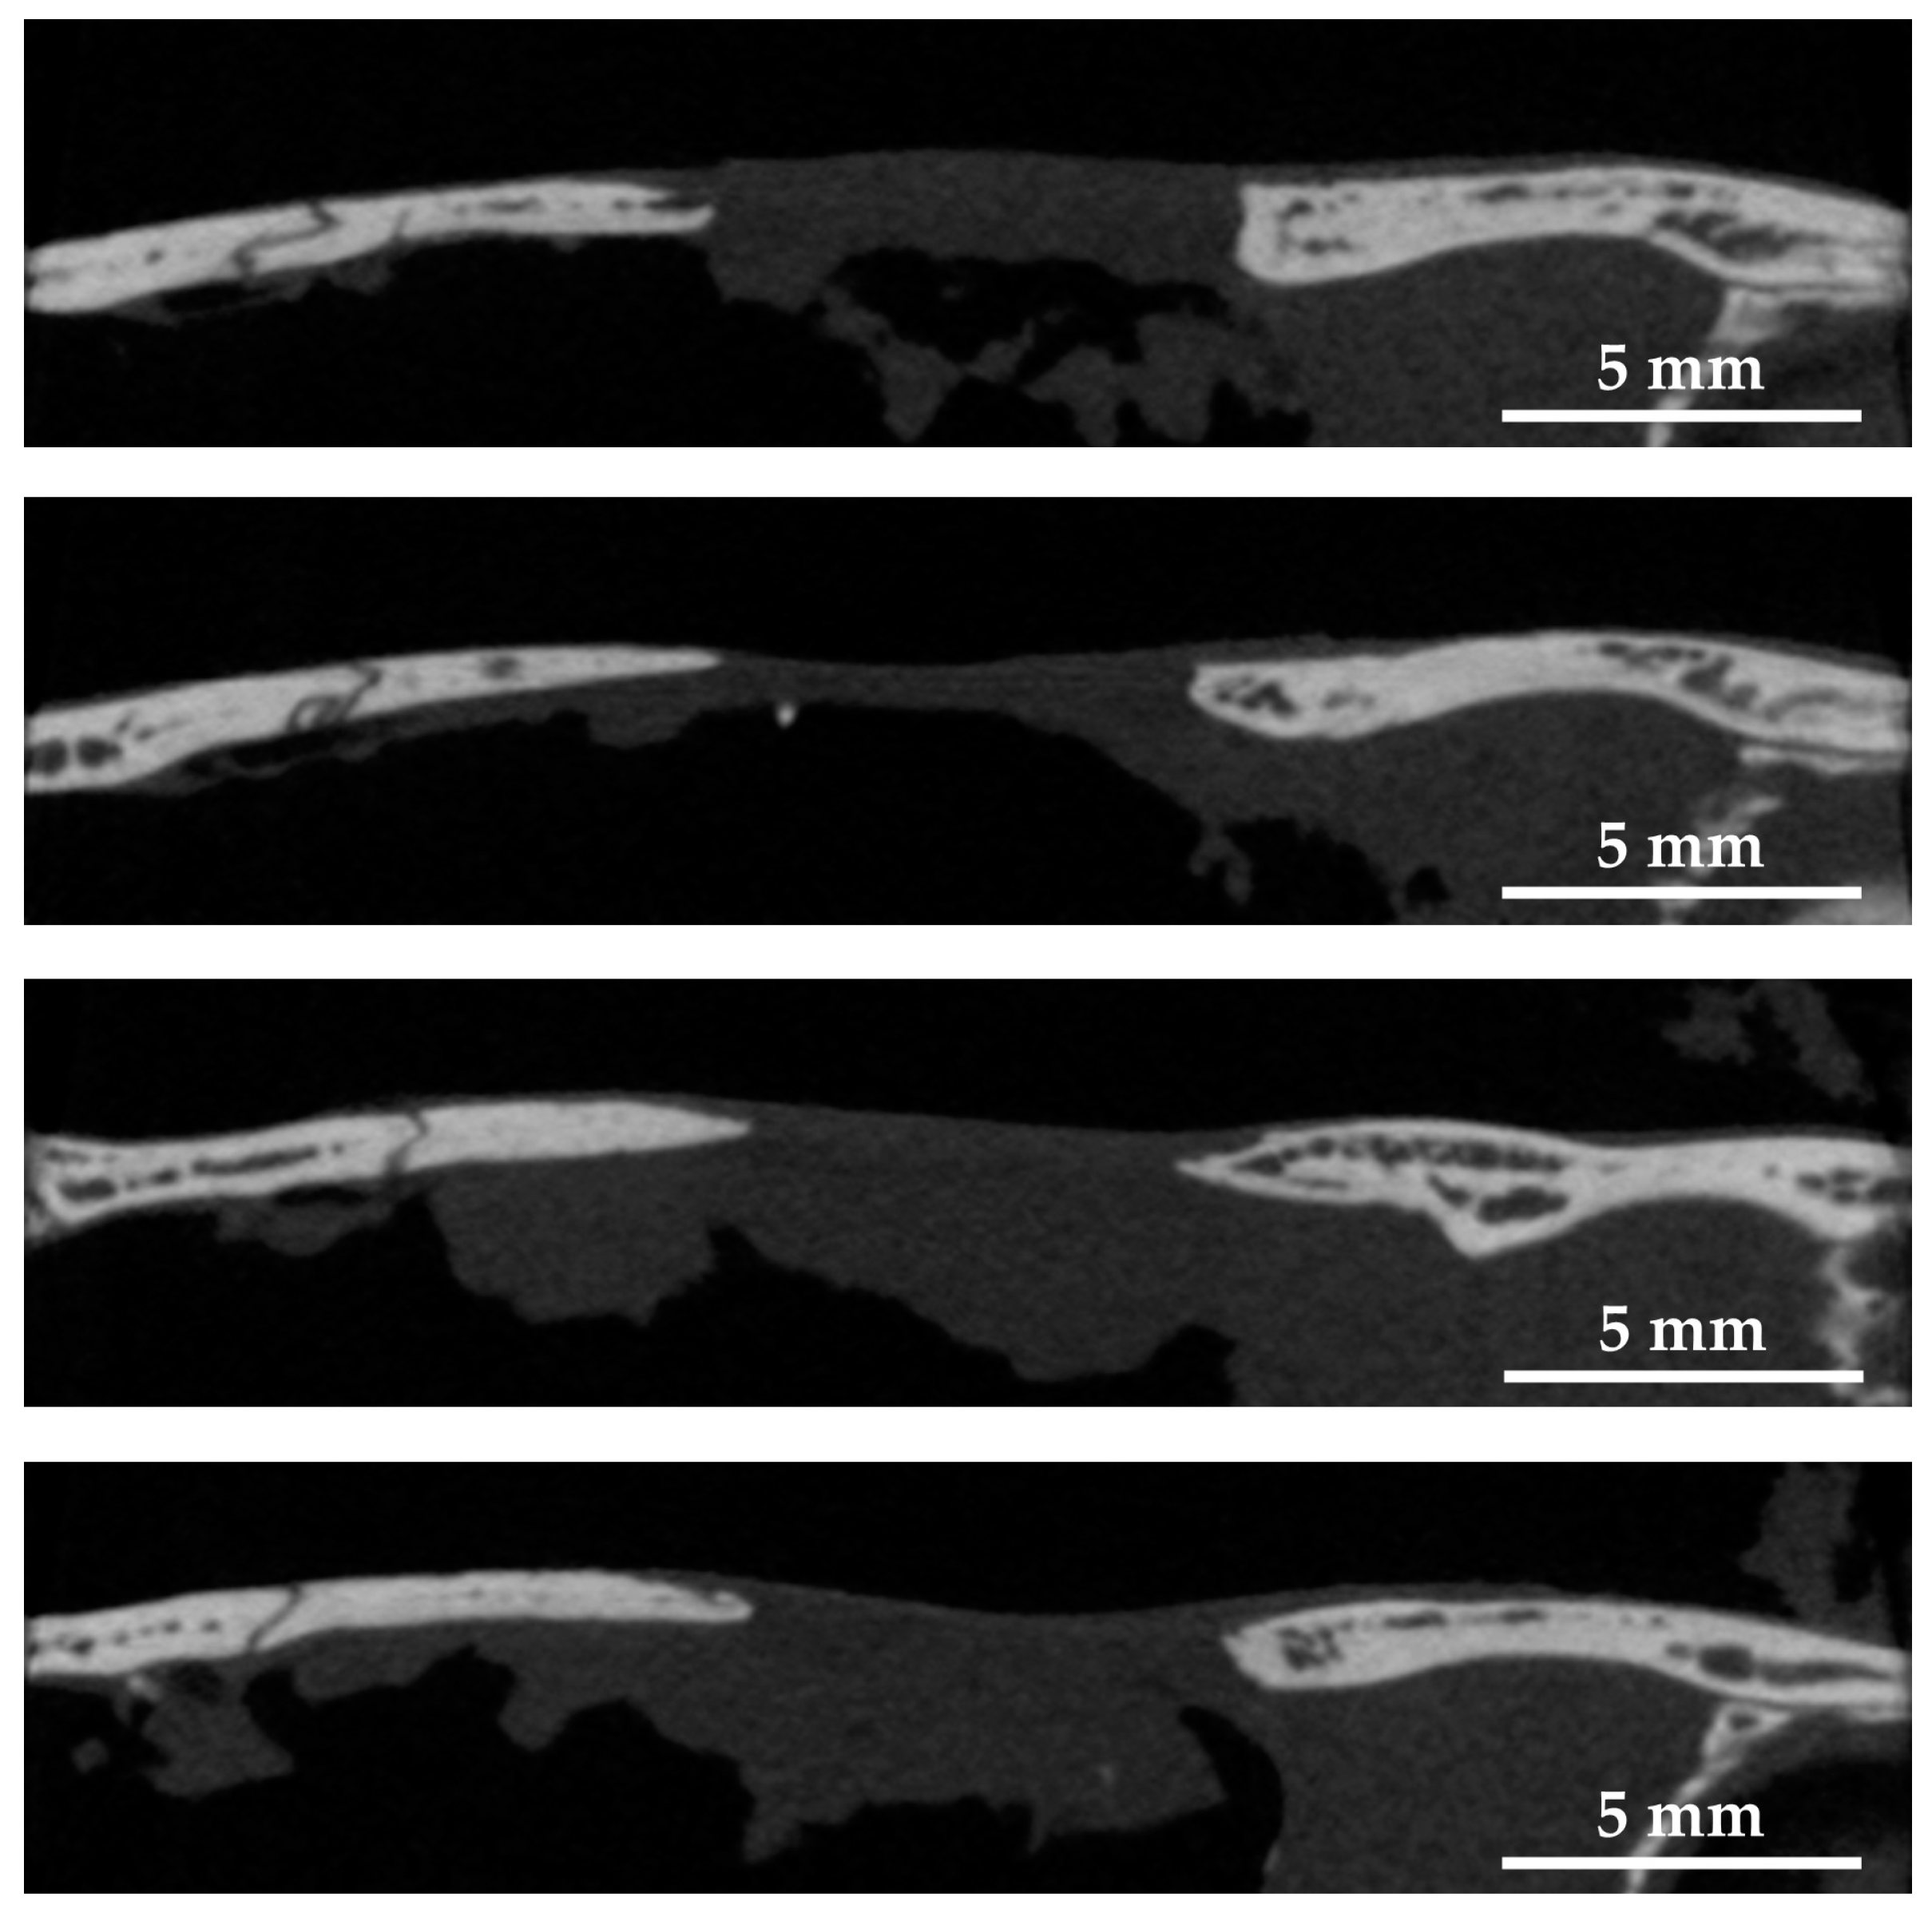

2.3.2. Micro-Computed Tomography (Micro-CT) Observation